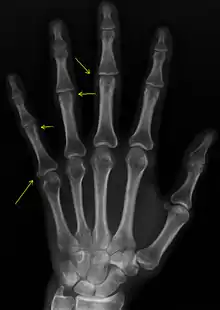

Sclerodactyly

Though it is the most easily recognizable manifestation, it is not prominent in all patients. Thickening generally only involves the skin of the fingers distal to the metacarpophalangeal joints in CREST. Early in the course of the disease, the skin may appear edematous and inflamed. Eventually, dermal fibroblasts overproduce extracellular matrix leading to increased tissue collagen deposition in the skin. Collagen cross-linking then causes a progressive skin tightening. Digital ischemic ulcers commonly form on the distal fingers in 30-50% of patients.[3]